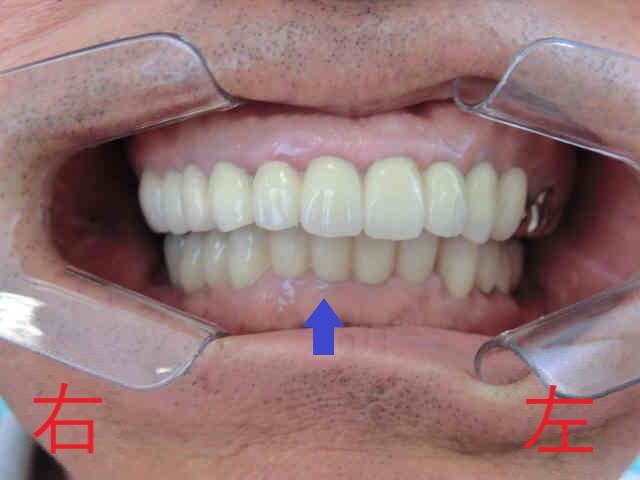

上記はインプラント治療を含めたすべての治療が終了した写真です。ここでも、青色矢印の下顎前歯の部分にご注目ください。冒頭の写真と比較すると、奥歯で噛んだ際に上顎前歯によって隠れていた下顎前歯の部分が少なくなっていることがお分かりいただけると思います。

歯ぎしりや食いしばりによってすり減った歯を被せ(冠)にすることで、咬合高径を引き上げ、“出っ歯”のように見えていた上顎前歯を内側へ移動させることができました。

「噛み合わせを高くすると、口を閉じにくくなるのでは?」とご懸念の方もいらっしゃるかもしれません。そこで、被せる前に仮歯を装着し、噛み合わせを綿密にチェックしております。実際、この患者様は通常通りに口を閉じることができ、口元の“出っ歯感”も解消され、自然な口元になりました。

つまり、この噛み合わせの高さこそが、患者様本来の高さだったということになります。